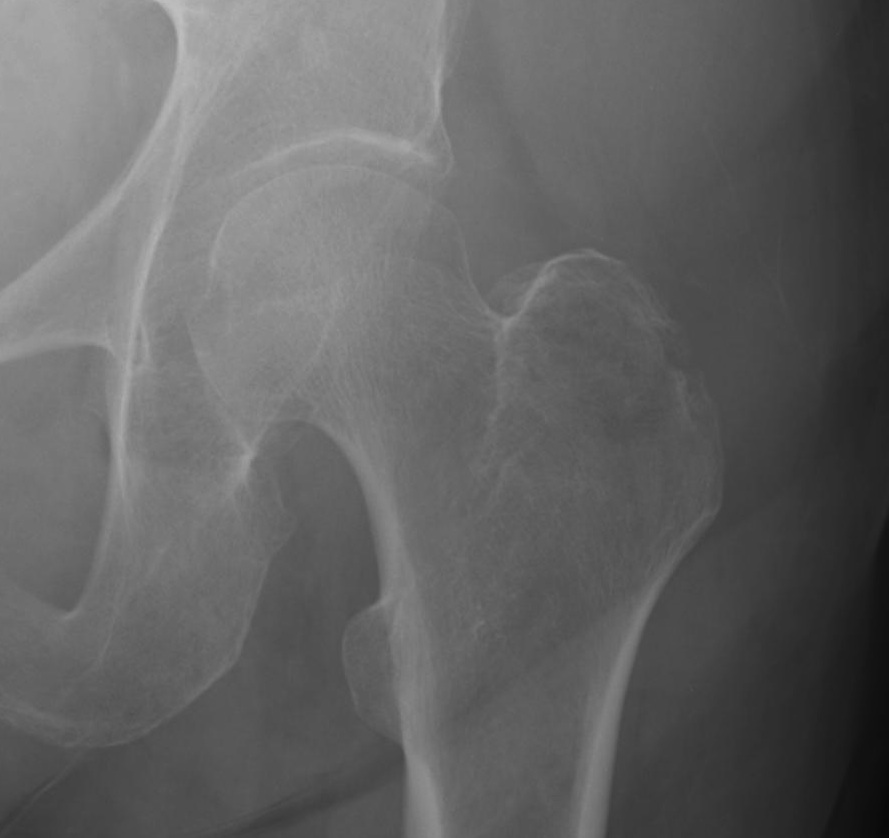

Cephalomedullary nail / Proximal femoral nail

Mechanical advantages

- load sharing rather than load bearing

- decreases lever arm

- supports medial cortex

Surgical advantages

- smaller incision / minimally invasive

- reduced blood loss

- shorter surgical times

Indications

- reverse oblique

- unstable fracture / loss of lateral buttress / loss posteromedial support

- subtrochanteric extension